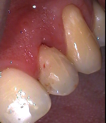

Conventional Treatment with Standard Core Restoration

Non-surgical endodontic treatment with resin core build up